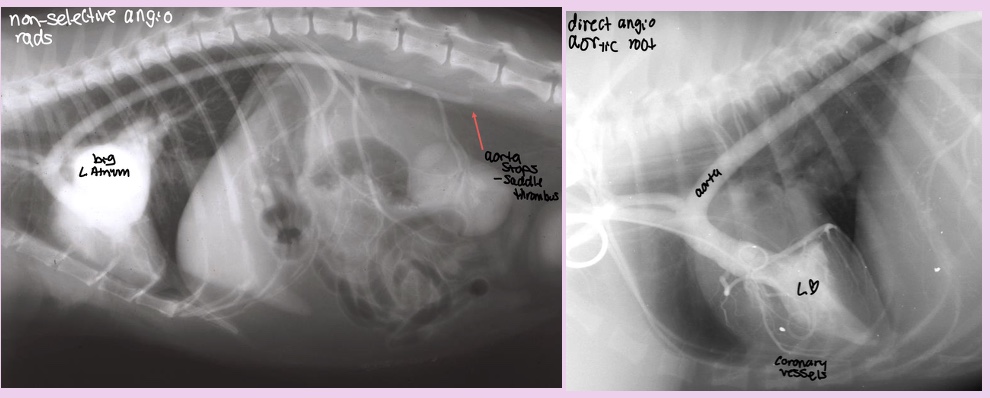

What does the angiocardiography highlight in pulmonic stenosis

-RV hypertrophy

-narrowing pulmonary outflow tract

-post-stenotic dilation of MPA segment

What disease does this dog have

Pulmonic stenosis

What does the angiocardiography highlight in aortic stenosis

-AA bulge

-increased cardiac waist

-left ventricular hypertrophy

-narrowing of aortic outflow tract

-post stenotic dilation of AA

± mitral regurg

Aortic stenosis

What does the angiocardiography highlight in PDA

-see the shunt

-left ventricular dilation

-opacification of aortic and pulmonary arteries

PDA